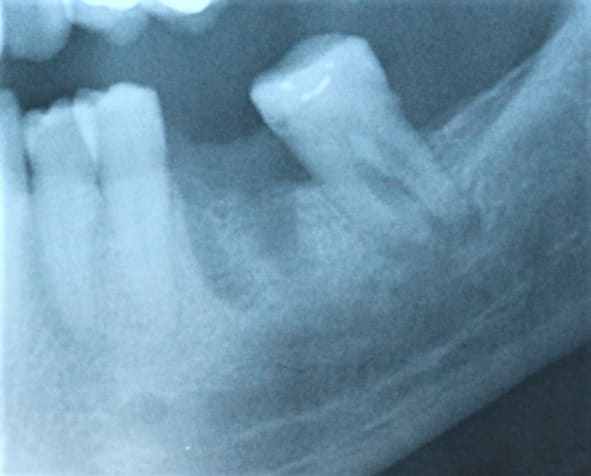

On voit quand meme assez bien sur la radio une lésion inter-radiculaire. Je ne vois pas trop l'interet de ce cas, enlaye, qui finit de toute facon un jour ou l'autre au davier :-)))

Replacée!!!! Felicitations. Et tu n'as pas vu une lesion qualque part au niveau du plancher?

on voit le pb sur la pano du 1er rdv .

pour ça que j étais parti sur une extraction réimplantation , pour nettoyer tout ça et bien re- esquicher la furcation dans l os , en coupant les racines .